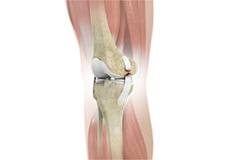

There are two major muscles in the knee - the quadriceps and the hamstrings, which enable movement of the knee joint. The quadriceps muscles are located in front of the thigh. When the quadriceps muscles contract, the knee straightens. The hamstrings are located at the back of the thigh. When the hamstring muscles contract, the knee bends.

Tendons of the Knee

A tendon is a tissue that attaches a muscle to a bone. The quadriceps muscles of the knee meet just above the patella and attach to it through a tendon called the quadriceps tendon. The patella further attaches to the tibia through a tendon called the patella tendon. The quadriceps muscle, quadriceps tendon, and patellar tendon all work together to straighten the knee. Similarly, the hamstring muscles at the back of the leg are attached to the knee joint with the hamstring tendon.